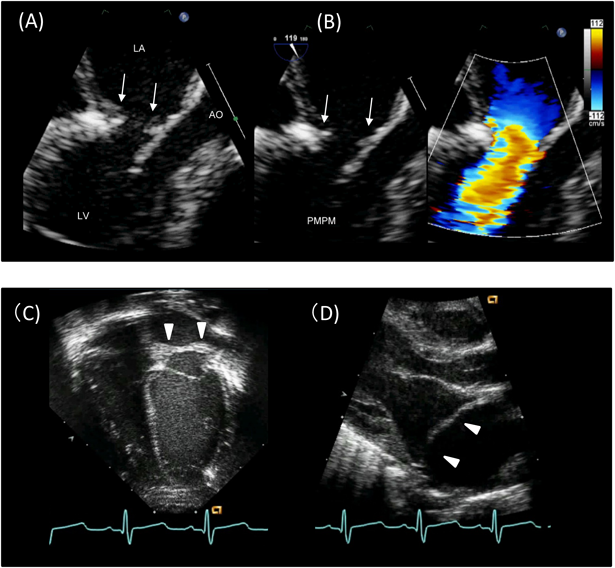

(5) 僧帽弁上狭窄輪(supramitral ring(supra-annular mitral ring/supra-valvular mitral stenosis)(Fig. 8)

Pediatric Cardiology and Cardiac Surgery 33(2): 140-156 (2017)

Fig. 8 Supramitral ring

(A) and (B) Transesophageal echocardiography of the supramitral ring (intramitral variant). Arrows indicate membranous structures adhering to the atrial side of the mitral leaflet, which restrict the opening of the leaflets. Note the accelerated flow at the supramitral ring. (C) Apical four-chamber image of the supramitral ring (supramitral variant). (D) Long-axis image of the supramitral ring (supramitral variant). Arrowheads indicate the supramitral ring, which is located below the orifice of the left atrial appendage. AO: aorta; LA: left atrium; LV: left ventricle; PMPM: posteromedial papillary muscle.

僧帽弁の左房側に発生した膜状の結合織が僧帽弁上で弁口を取り囲むように狭窄輪を形成する.この狭窄輪は僧帽弁の左房面に付着した膜様構造物として弁尖の解放を制限する場合(intramitral variant)(Fig. 7A&B)と,僧帽弁とは離れて弁上に輪状構造として存在する場合(supramitral variant)(Fig. 7C&D)が存在する.狭窄輪は左房内で左心耳や卵円窩よりも僧帽弁側に位置し,このことが三心房心(cor-triatriatum sinister)との鑑別点となる.本病変が単独で存在することは稀で,多くは合併心奇形を有する.特に,大動脈縮窄に加えて複数の左室内狭窄病変(僧帽上狭窄輪,パラシュート僧帽弁,大動脈弁下狭窄)を合併したものをShone complex(syndrome)と呼ぶ.